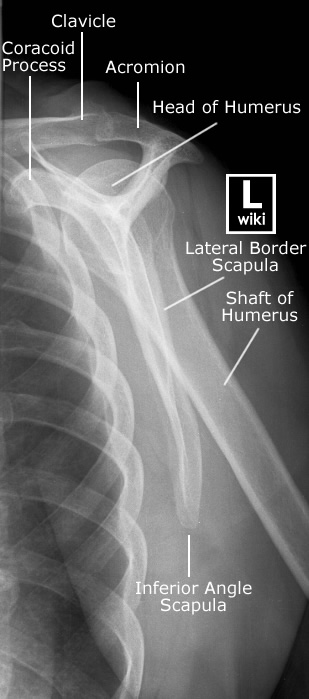

Spine Radiographic Anatomy

| AP view (Cervical) | AP view (Thoracic) |